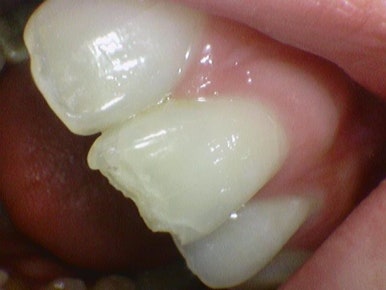

Case 3.

라미네이트가 깨져서 급하게 오신

외국인 관광객 환자분이었습니다.

라미네이트가 깨진 경우 원래는 다시 라미네이트나 크라운 등

라미네이트 이상의 치료를 하셔야하는데 출국하셔야 하는 해외환자분이라

레진으로 임시로 해드렸고 환자분께서 신세계 를 경험하셨다고 하셨습니다!